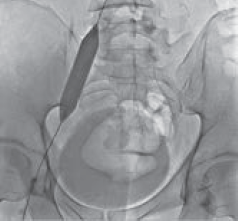

Рис. 4. Антеградная илеокаваграфия пациента М., 39 лет, от 28.03.2017. Отмечается компрессия левой общей и левой наружной подвздошных вен. Оперативный доступ из левой подколенной вены. Положение пациента на животе